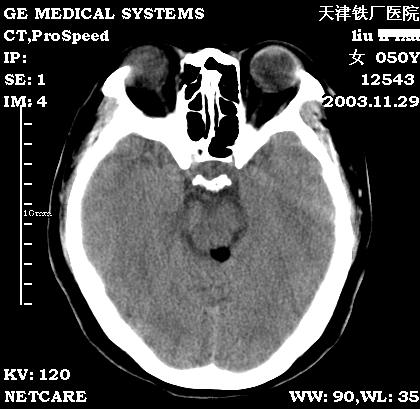

四叠体池脂肪瘤

患者:女,患者头部不适,前来就诊。

zzzsssjjj发言:考虑四叠体池脂肪瘤,该病1856年由rokitansky首先报道,此病属先天性病变,属神经管闭合异常畸形,常见于胼胝体,也可发生四叠体池、鞍上池等,其边缘也可钙化。

1、部位:四叠体池,为脂肪瘤的好发部位

2、常合并其他部位的先天畸形。

3、鉴别诊断:于畸胎瘤和皮样囊肿鉴别

结果:患者在天津环湖医院行mri检查也考虑:脂肪瘤